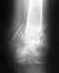

Возраст женщины 84года. Сломана шейка бедра.

Возможна ли операция, или какое-то другое лечение? Стоимость операции, сроки, предполагаемый прогноз на выздоровление.